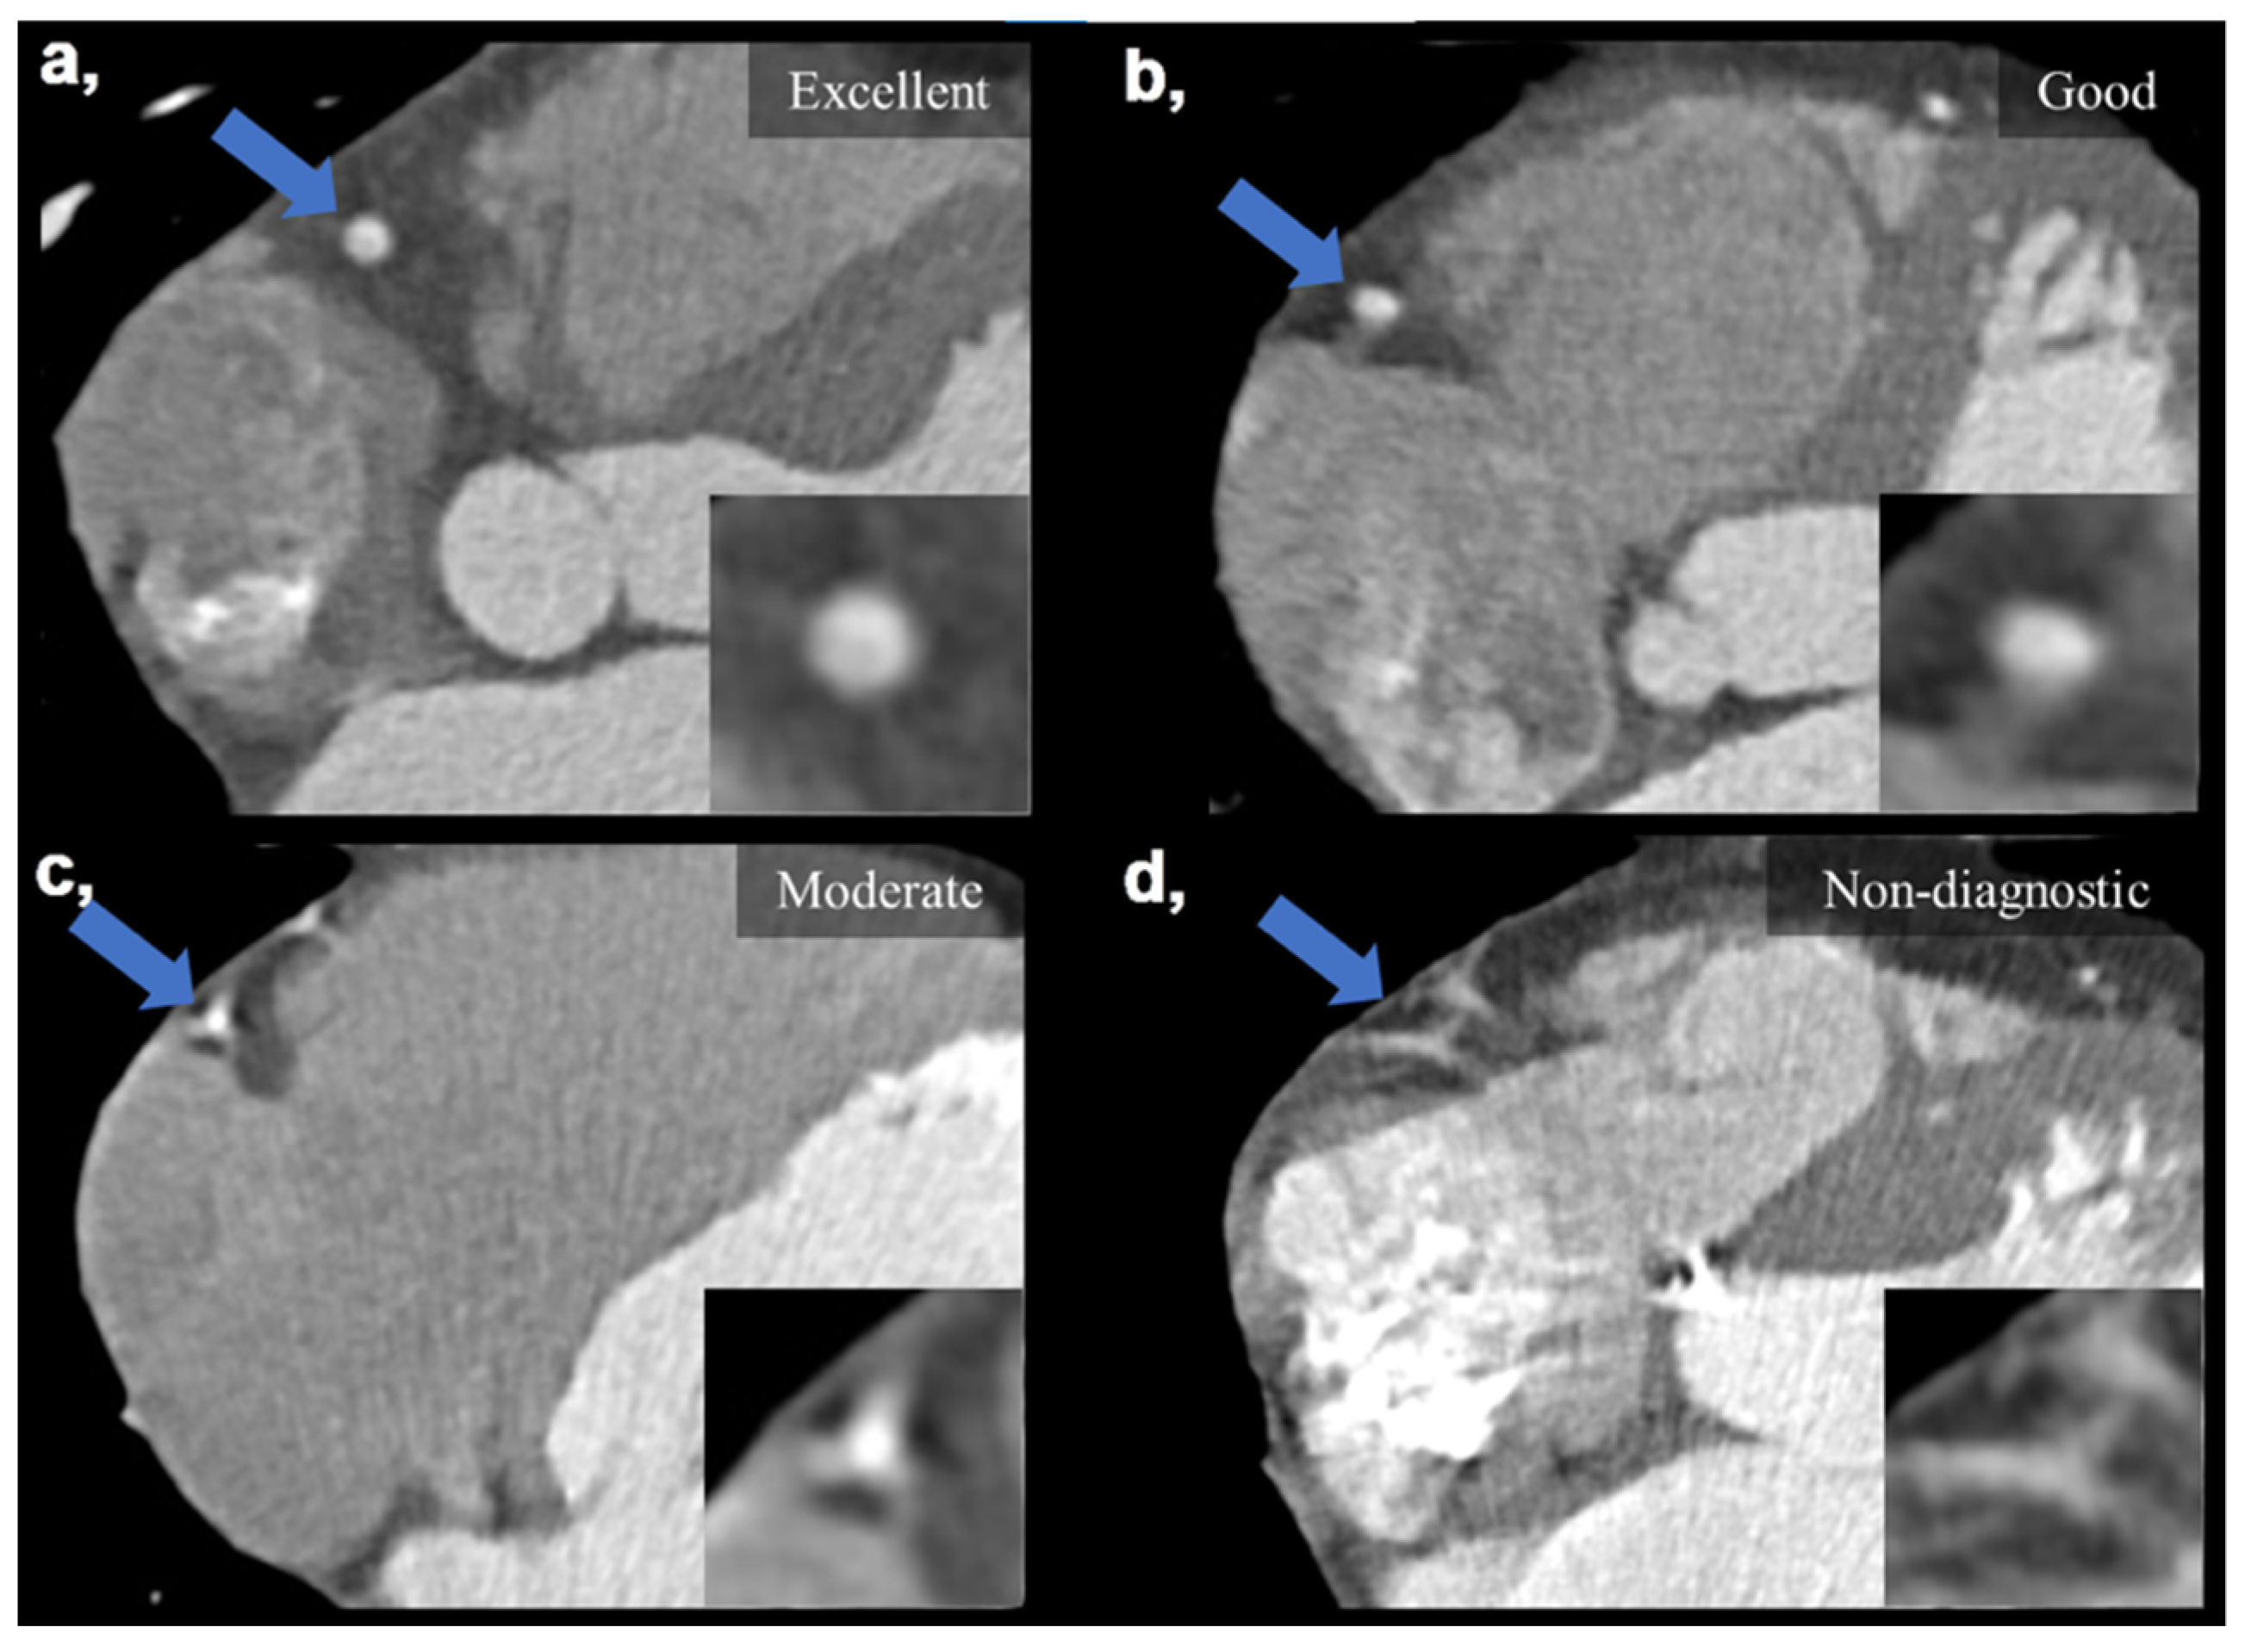

Subjective IQ was evaluated using the best reconstruction phases (predominantly end diastolic 78–81%) selected by the examiners. IQ was graded on a four-point Likert scale considering the degree of motion artifacts affecting the evaluation of the coronaries: (1) non-diagnostic, with severe motion artifacts seriously impairing evaluation; (2) moderate, with considerable motion artifacts, resulting in an IQ only sufficient to rule out significant luminal stenosis; (3) good, with preserved ability to assess the degree of lumen stenosis and (4) excellent, with no visible motion artifacts and sharp vessel contours (Figure 2). Interpretability was defined on a per-patient basis: if an evaluated coronary artery was rated as non-diagnostic, the corresponding patient was considered non-interpretable. The readers were instructed to ignore issues that could not be ascribed to the presence of motion artifacts (e.g., prominent image noise, poor contrast, extensive calcification or step artifacts). IQ assessment was performed as part of a clinical reading by four experienced cardiovascular radiologists (with >8 years of experience in reporting CCTAs). Assessment was carried out in each case with respect to our institutional standards. Reliability of the assessments is ensured by regular monthly consensus reads. Reproducibility between readers was assessed using a sample of 20 datasets to calculate Fleiss’ kappa value.

Figure 2.

Visual representation of image quality categories on four example images taken on the DCCT. (a) Excellent IQ with sharp vessel contours and three grades of motion artifacts degrading the evaluation of the right coronary artery (b–d). (b) Good IQ—slight motion artifact not affecting luminal assessment. (c) Moderate IQ—only the presence of significant stenosis can be ruled out. (d) Non-diagnostic IQ—no luminal assessment is possible. Blue arrows mark the middle segment of the right coronary artery, which is also enlarged in the right lower corners of the images. DCCT: dedicated cardiac CT, IQ: image quality.